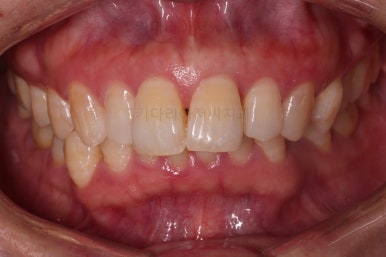

마무리 사진이에요.

치열이 매우 가지런해졌고, 틈도 없고, 앞니의 뻗친 느낌도 사라졌네요.

교합도 좋고요.

삐뚤고 솟구쳐 있던 치열도 가지런하게 되었고, 틈새도 다물어졌으며 뻗쳐 있던 느낌도 개선이 되었어요.

18개월의 기간동안 부산성인교정 많은 점들이 개선되 만족스러운 치료결과였어요.